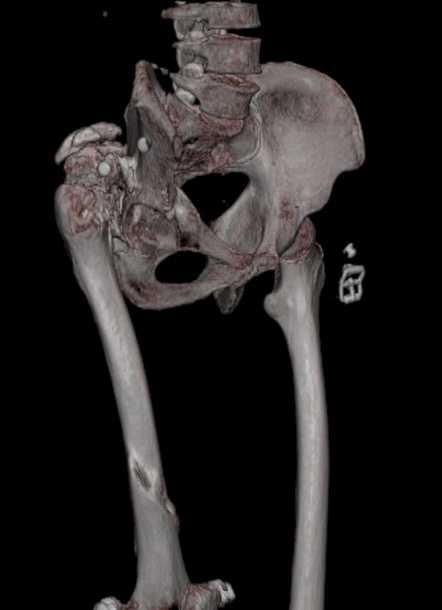

Пациент 30 лет 3 года назад в результате травмы получил травматический

дефект нижних конечностей до в/3 голеней, был пропущен вывих бедра. В настоящее время очень

неплохо ходит на протезах, движения в неоартрозе близки по объему к здоровой стороне.

Основная жалоба - выраженная боль при ходьбе. планируем двухэтапное эндопротезирование -

задним доступом мобилизовать проксимальный отдел бедра, резецировать шейку, аппаратом

низвести бедро(головку оставить там где она есть, так как больших дефектов не видно(может

пригодится в последующем?)). Вторым этапом бесцементное эндопротезирование. Насколько

такой вариант реалистичен? Доступ для второго этапа? Может быть, другие варианты?